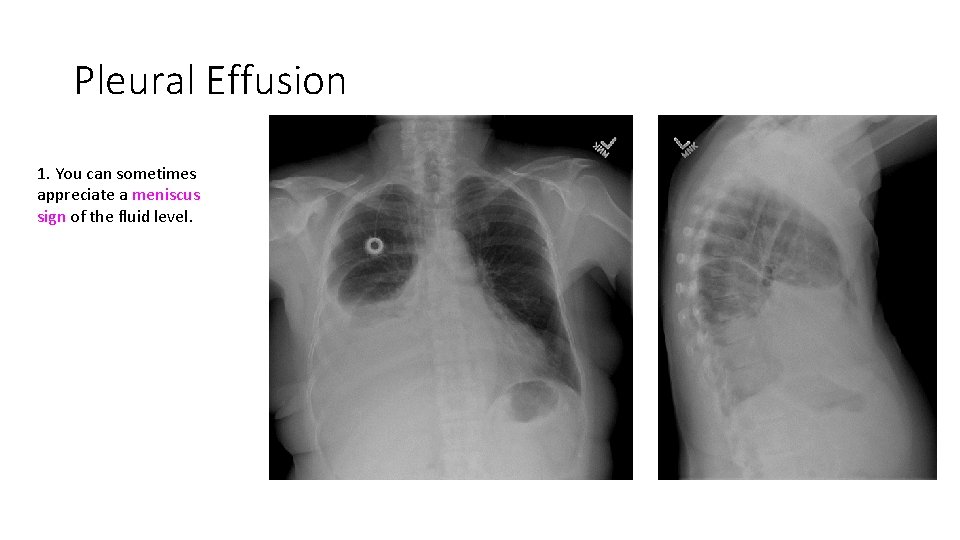

Pleural Effusion 1. You can sometimes appreciate a meniscus sign of the fluid level.